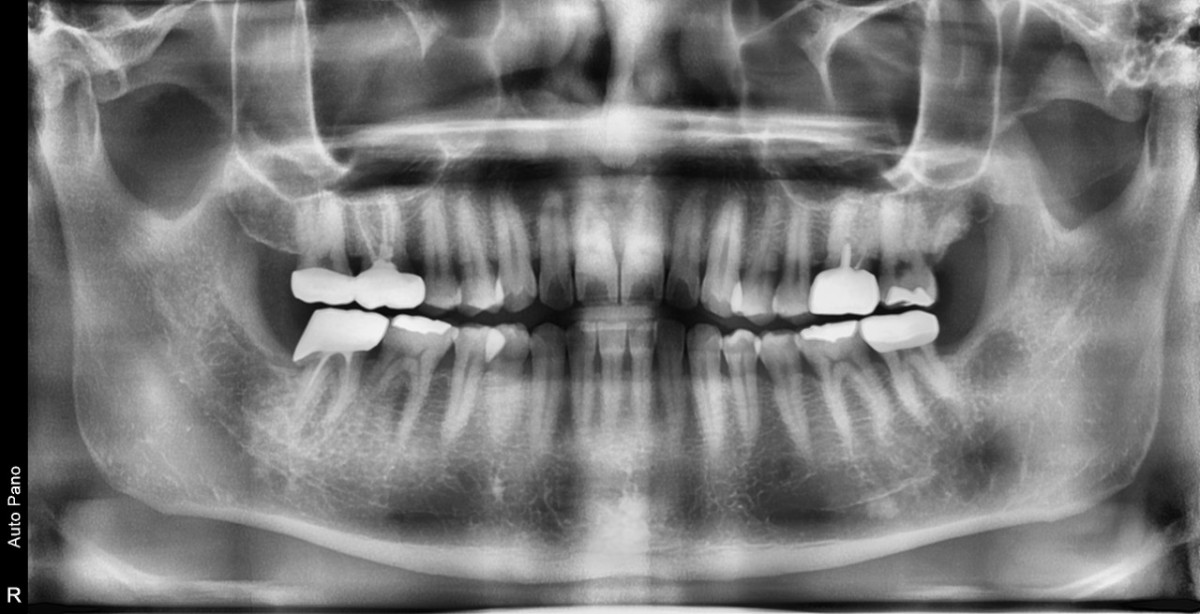

A 47-year-old male patient had a crown with an ill-fitting margin and crack-tooth syndrome in the lower 2nd molar. No systemic issue.